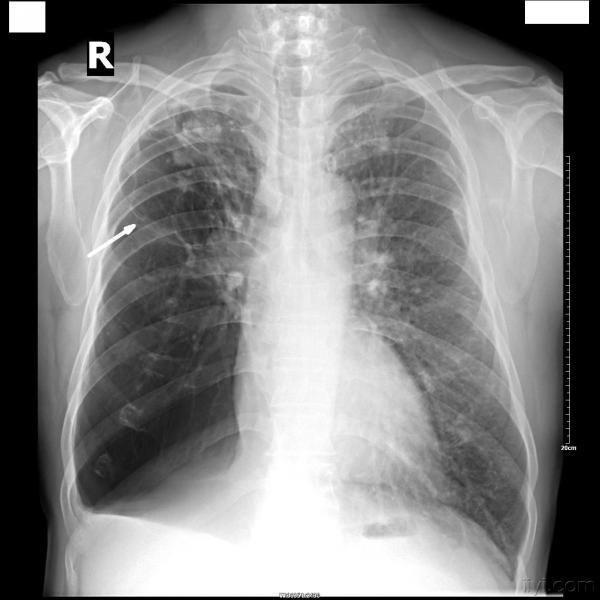

患者,男,59岁,有肺结核病史多年,现咳嗽、气喘,加重一天。

常规胸部正侧(右)位片如下:

发此贴的真正意义是:肺大泡和包裹性气胸的鉴别诊断。

该患者右上肺有胸膜粘连,单纯一张正位片上不排除右下包裹性气胸的诊断,但侧位片未发现粘连胸膜及压缩肺组织边缘,所以右下仍然考虑:巨大肺大泡。